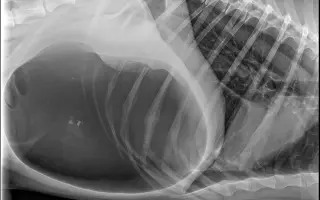

Pomozte Inukovi a jeho majitelce změnit tento příběh